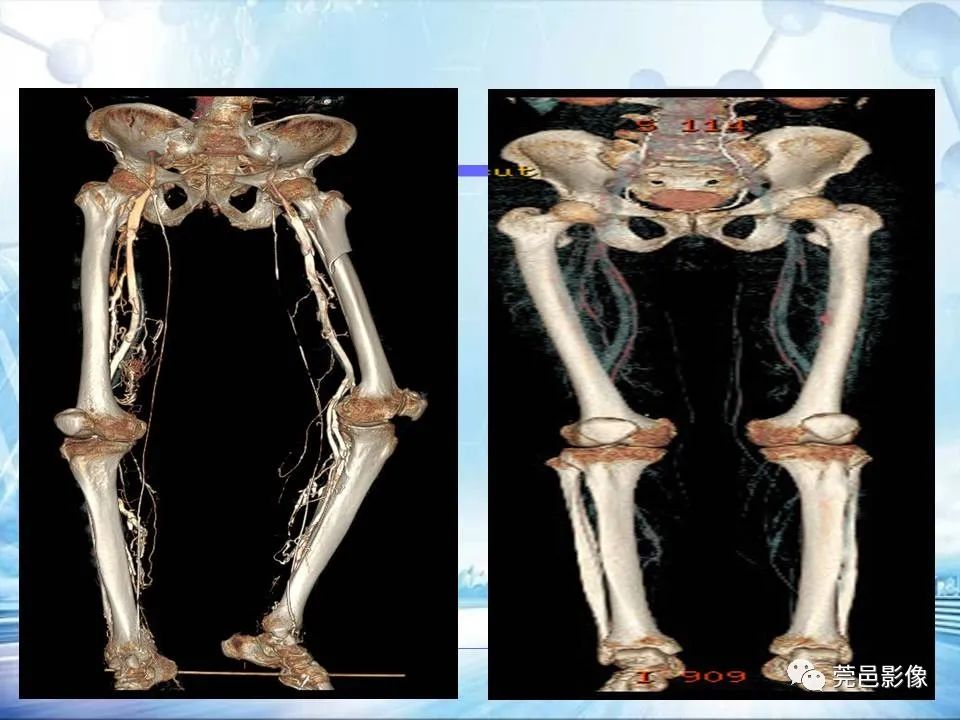

浅谈下肢静脉CTV的应用体会